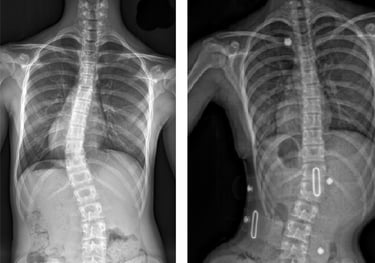

Scoliosis is often first noticed by parents or close family members, as the shoulders or pelvis may appear uneven. A thorough physical examination is conducted to assess posture, gait, and spinal alignment. The Adams Position Test, which involves the patient bending forward to reveal any visible curvature, is commonly used to assess scoliosis. If a noticeable curve is detected, an X-ray is typically ordered to determine the severity of the condition.